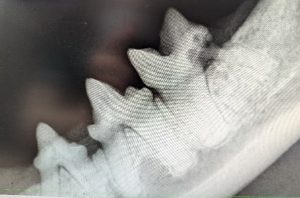

In these images, on the left we have a healthy set of teeth whereas on the right we are beginning to see resorption of the furthest back tooth. This may have been difficult to see without imaging, as it is not a severe level of resorption and may have been covered up by gum inflammation.